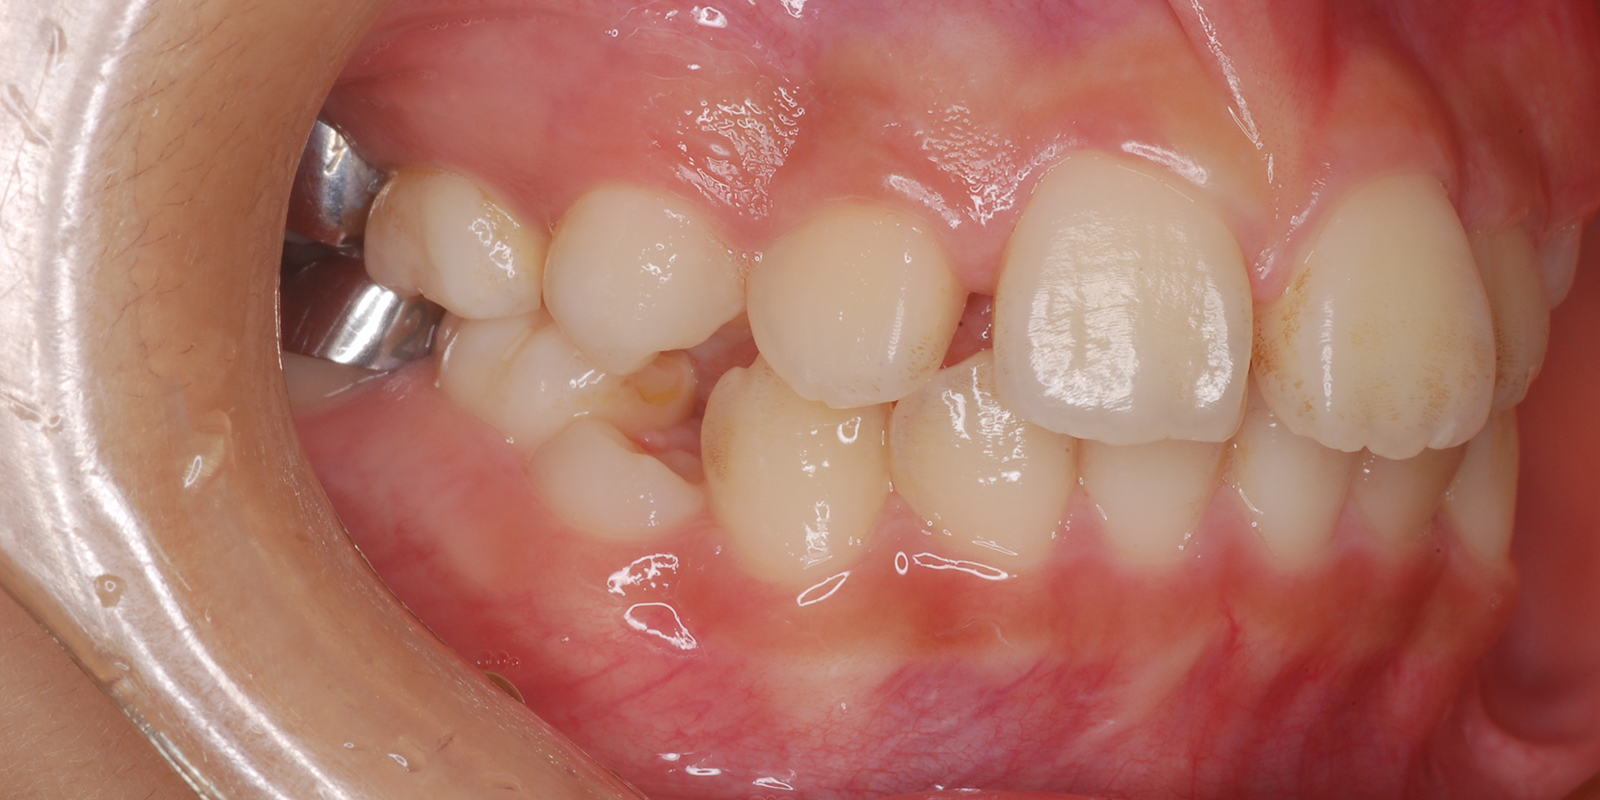

術前

| 主訴 | 噛み合わせが深い |

| 診断 | アングルⅡ級2類Deep bite |

| 初診時年齢 | 8歳3か月 |

| 装置 | EF |

| 抜歯・非抜歯 | 非抜歯 |

| 治療期間 | 2年 |

| 通院回数 | 約12回 |

| 治療費 | 25万円 矯正歯科治療は公的医療保険の適用外の自費(自由)診療となります |

| 治療のリスク | ・装置を使用しなければ効果が出ない ・上下前歯に痛みが出ることがある ・取り外しのためなくすことがある |